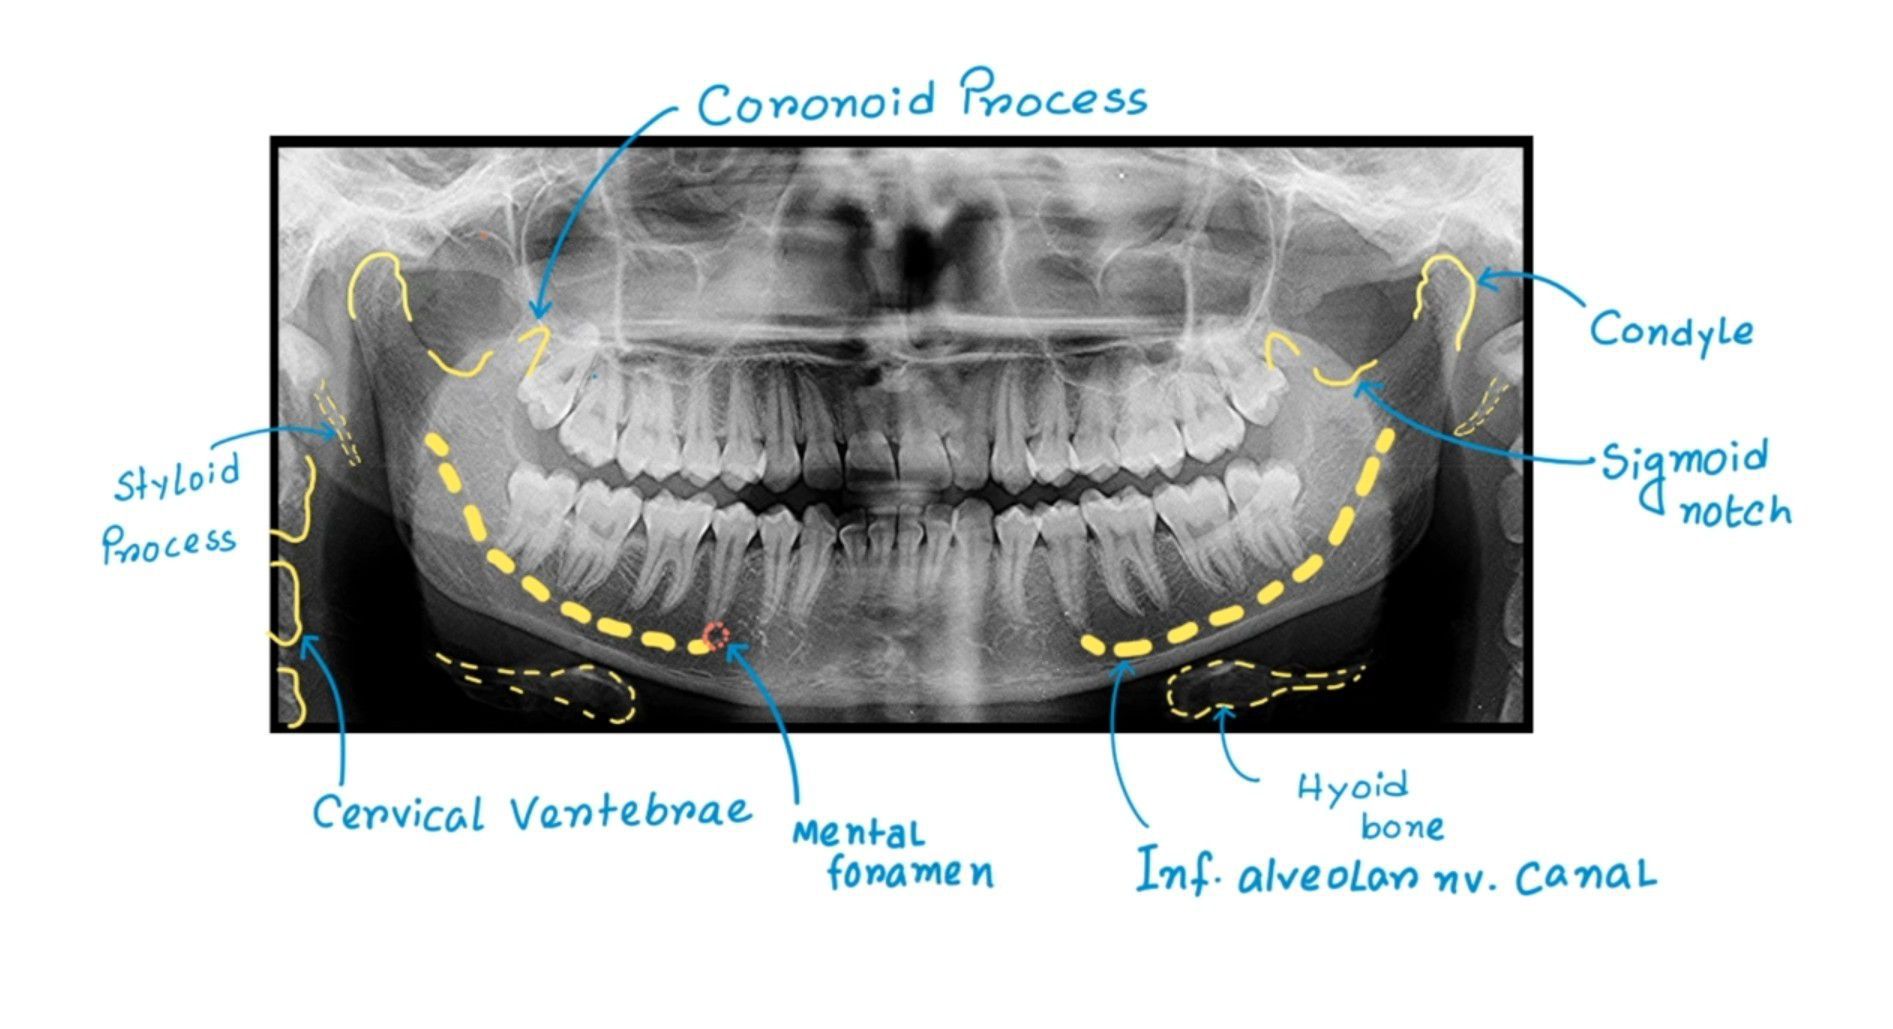

OPG Interpretation

Here is an easy guide to OPG.